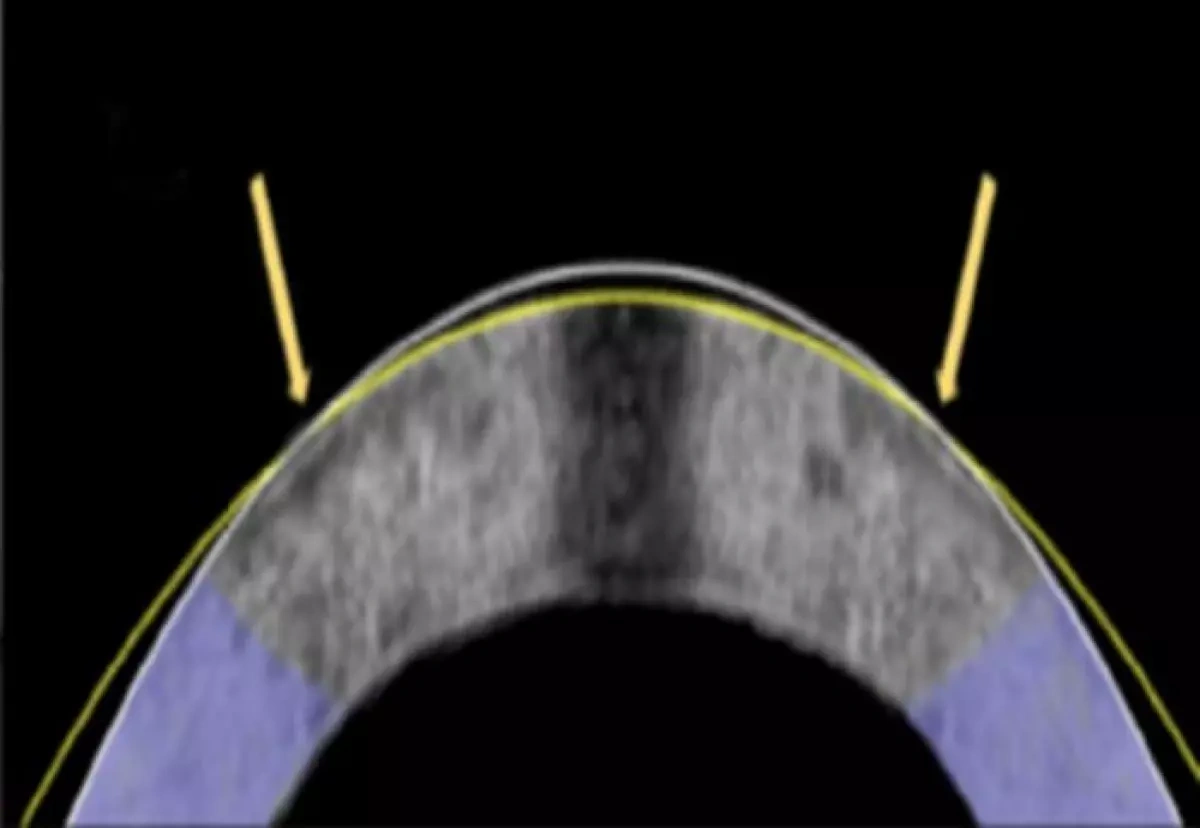

Измененная с помощью электромеханической коррекции роговица кролика, показанная в поперечном сечении. Первоначальная форма — белая линия, скорректированная — желтая линия.

За счет слабых токов специалистам в ходе испытаний удалось изменить pH ткани, увеличив кислотность роговицы, обеспечив ее податливость к принятию новой формы. В качестве этой формы и выступает платиновая линза. После отключения тока pH роговицы восстанавливается и она затвердевает — зрение восстанавливается.